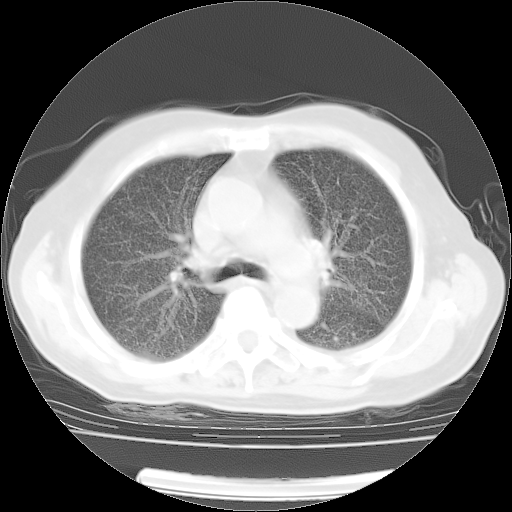

4月14日肺部CT

23.JPG

24.JPG

25.JPG

26.JPG

肺部CT平扫未见异常。